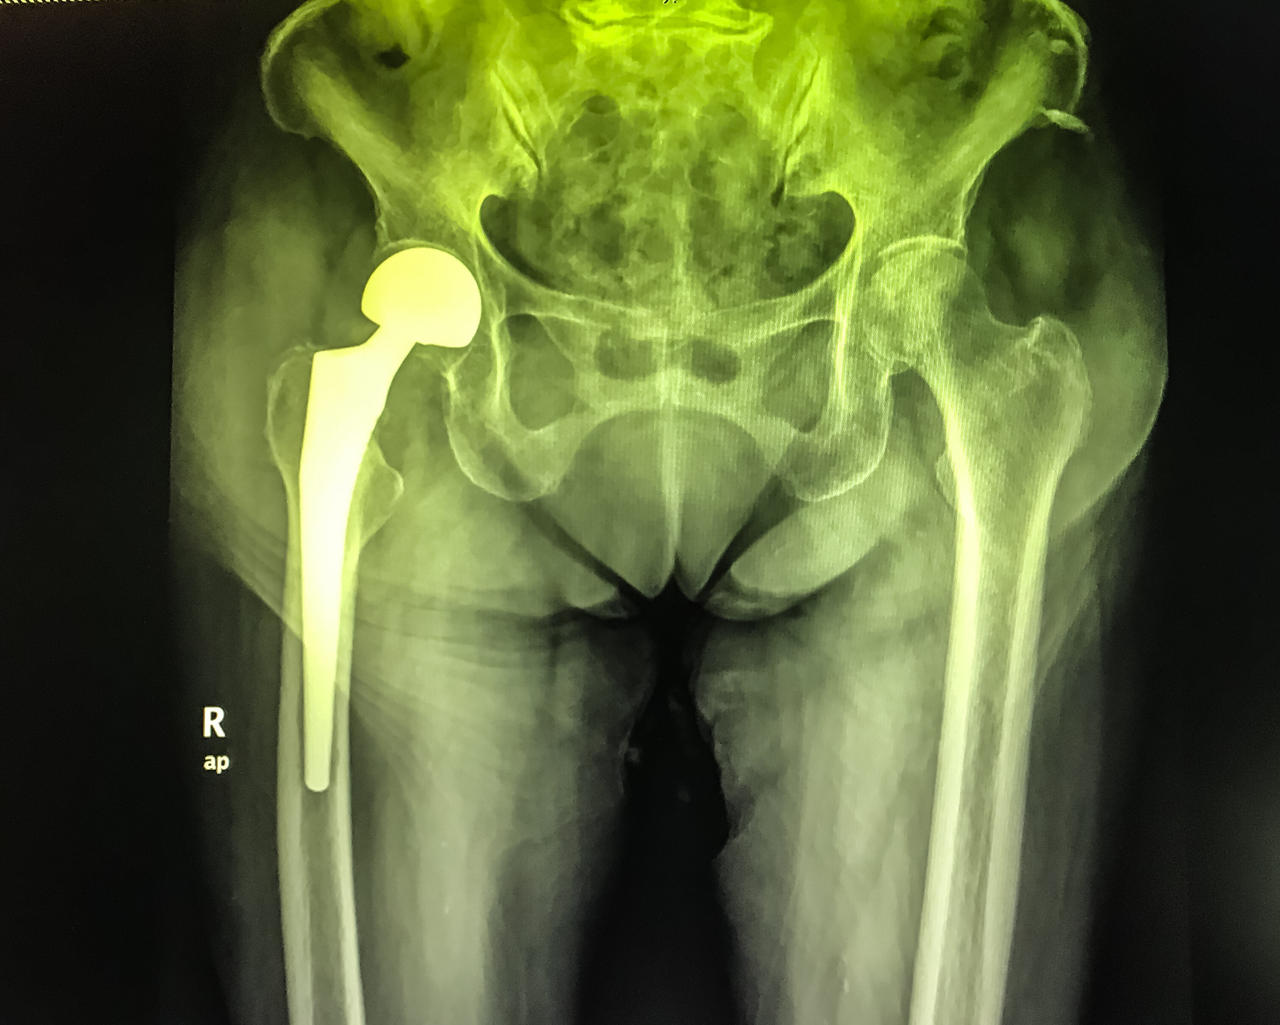

- Ai soggetti osteoporotici portatori di protesi d’anca.

La frattura al femore è il caso più drammatico di osteoporosi severa. Essa è indice del fatto che l’osteoporosi ha alterato in maniera significativa la resistenza del nostro tessuto scheletrico aumentando la fragilità ossea portando a questo evento traumatico.

Queste fratture spesso richiedono un intervento chirurgico per la loro riparazione.

Una frattura al femore può anche ridurre il soggetto colpito in condizioni di disabilità fisica nel 20% – 30% dei casi.

Attenzione: perché il femore può subire ulteriori fratture dopo la prima: nei successivi 5 anni dalla prima frattura le probabilità di subirne una nuova salgono al 20%. E le possibilità che venga colpito da frattura il femore della gamba opposta salgono al 50%. Spesso la frattura al femore può richiedere una lunga degenza.

Le persone che hanno subito una frattura al femore prossimale presentano un tasso di mortalità del 15% – 30% entro un anno dalla frattura.